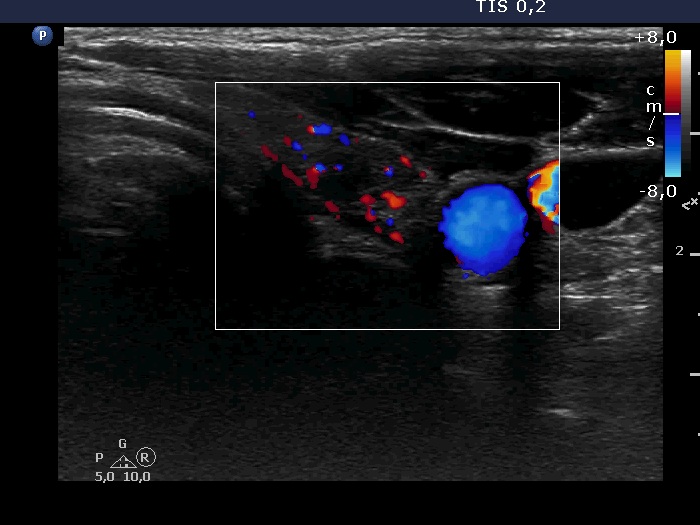

The borders of the nodule - case 1036

30 months after the initial examination (ultrasonographic picture 6)

Left lobe, transverse scan, color Doppler mode. The vascularization is a little bit increased.